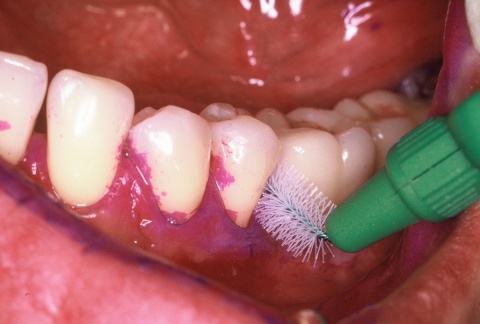

•IP1 – Mundhygienestatus: Darunter versteht man die Beurteilung der Mundhygiene mittels Anfärben der bakteriellen Beläge und der Benutzung eines geeigneten Index, z. B. des Approximalraumplaqueindex (Abb. 6). Für die Beurteilung des Gingivazustandes ist ebenfalls ein geeigneter Index anzuwenden, z. B. der Sulkusblutungsindex.

Im Regelfall werden die individualprophylaktischen Maßnahmen im Rahmen einer einsatzvorbereitenden Prophylaxesitzung durchgeführt. Die Besonderheiten des Einsatzes können Auswirkungen auf das individuelle Mundhygieneverhalten der Soldaten/innen haben, sodass die Durchführung der beschriebenen Maßnahmen im zeitlichen Zusammenhang zum bevorstehenden Einsatz sinnvoll ist. In Abhängigkeit von den jeweiligen klinischen Befunden kann die Entfernung harter und weicher Beläge in dieser Sitzung indiziert sein (Abb. 7). Die Entscheidung darüber trifft jeweils der SanOffz/Zahnarzt.